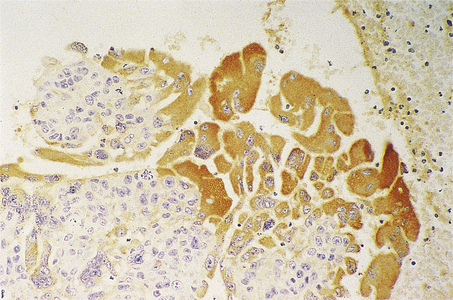

The great majority of tumours are adenocarcinoma, often described as microacinar, though much variety of histological pattern is recognised, and the tumours often show more than one pattern. Rare subtypes include an aggressive small cell carcinoma, which is similar to small cell lung cancer (Ch. 14), and large duct carcinoma, which arises centrally from the large ducts; these are not discussed further.

The Gleason grading system describes the usual patterns taken by the tumour. Gleason pattern 3 is the commonest pattern, and comprises separated, somewhat irregular, gland or acinar profiles, that infiltrate into normal glands at the edge of the mass. Gleason pattern 4 has fused glands or cribriform structures (Fig. 20.11), while in pattern 5 acinar differentiation is no longer apparent in strands of tumour cells, or there may be cribriform structures with central necrosis. It is now widely acknowledged that Gleason pattern 1 is probably not carcinoma, while pattern 2 is a generally small, well-circumscribed mass of regular glands; it is of limited clinical significance. The grading system is to note the dominant (primary) pattern and add the next most frequent (secondary) pattern to give a combined score; where only one pattern is seen (as often applies in a small biopsy) the number is doubled. Thus, the majority of prostate cancers are graded as Gleason 3+3=6; many are Gleason 3+4=7, while a particularly aggressive tumour would be Gleason 5+5=10.

image

Fig. 20.11 Histology of prostatic carcinoma. The tumour is an adenocarcinoma consisting of neoplastic glands infiltrating a fibrous stroma.